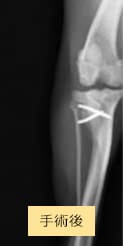

症例2

チワワ×マルチーズ(4歳10ヶ月齢、雌)

グレードⅡ〜Ⅲ 外科手術

- 【初診時症状】

- 他院にて両後肢パテラグレードⅢと診断。手術を希望されて受診

- 【手術】

- 滑車溝形成術、脛骨粗面転位術、関節包縫縮を実施

- 【経過】

- 性格的にご自宅での安静が難しいため、術後2週間入院。術後4週間で屋内での運動制限を徐々に解除、8週間でお散歩の距離を少しずつ伸ばしていくも問題なし。 現在は制限なく生活